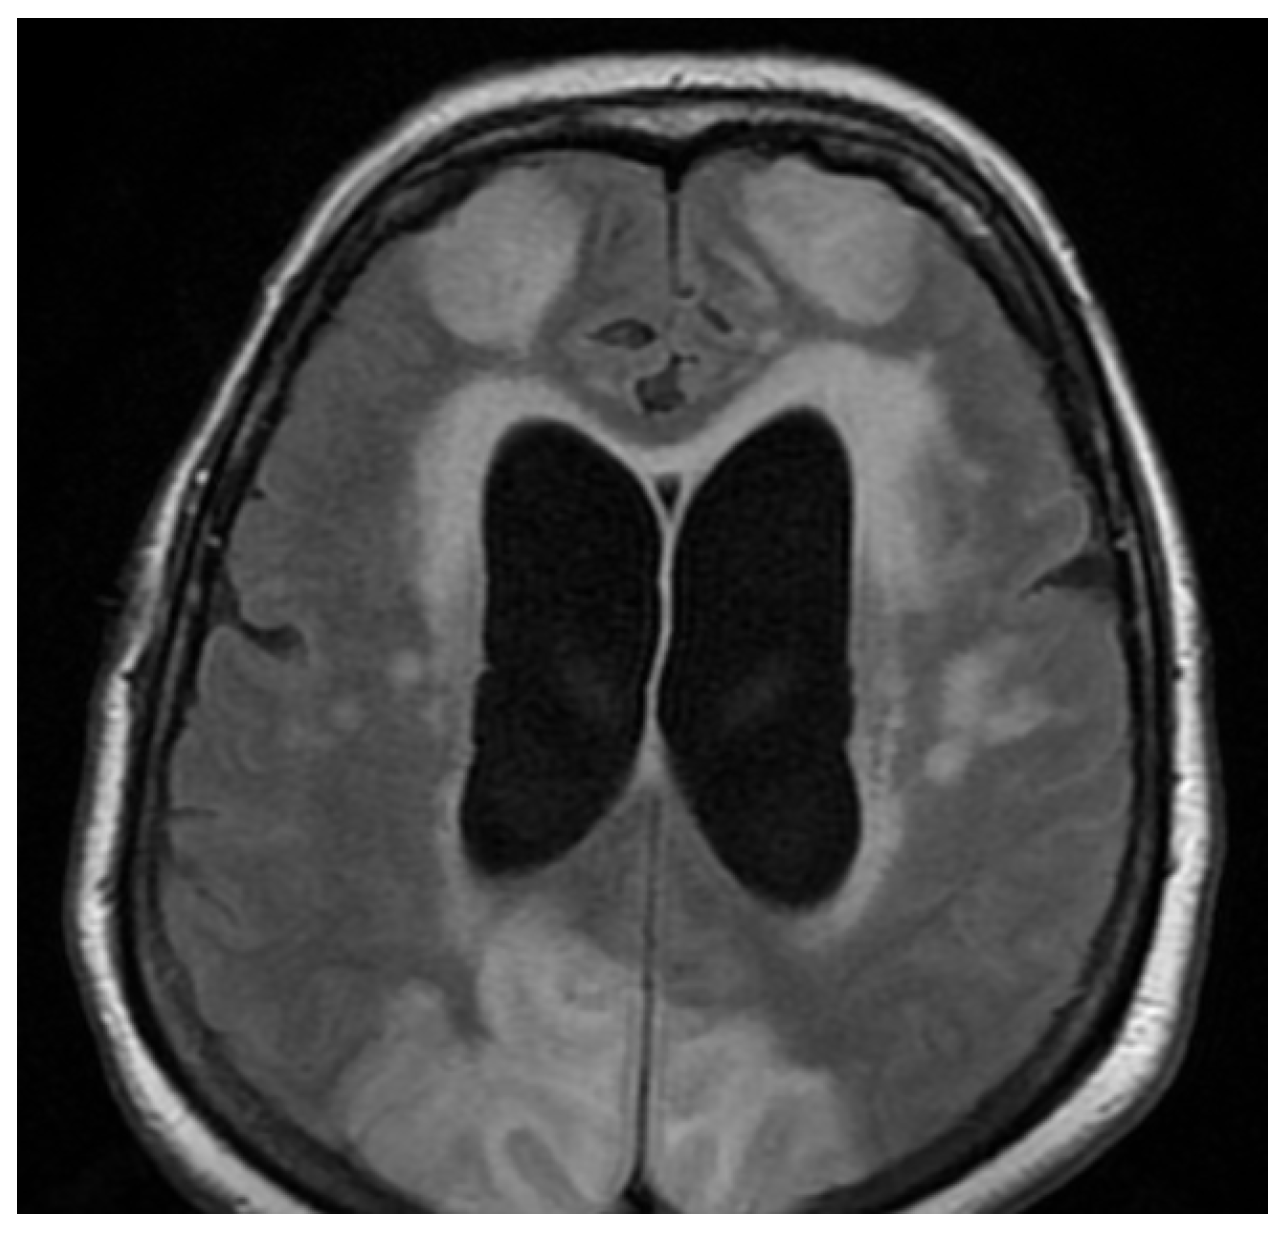

3.3. Neuroimaging